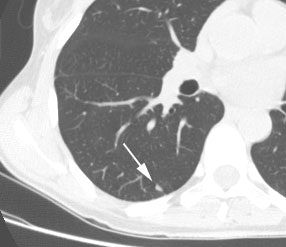

Bronchoalveolar cell carcinoma (BAC): The images below were from a patient with bronchoalveolar cell carcinoma that presented as a chronic right lung infiltrate. The FDG PET exam was positive in this case despite a higher likelihood of a false negative exams in patients with BAC. Note the most intense area of FDG accumulation corresponds to the area of greatest consolidation on CT imaging. |

|